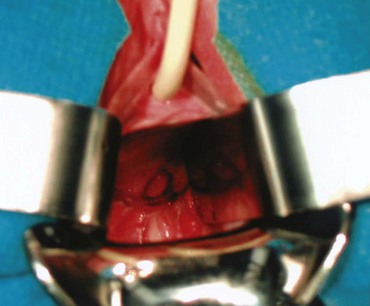

The etiology of VVF differs in various parts of the world. In the industrialized world, the most common cause (>75%) of VVF is injury to the bladder at the time of gynecologic, urologic, or other pelvic surgery (Symmonds, 1984; Lee et al, 1988; Tancer, 1992). Surgical injury to the lower urinary tract most commonly occurs in the setting of hysterectomy (Fig. 77–2), whereas most of the remainder are related to general surgery procedures in the pelvis, anterior colporrhaphy or cystocele repair, anti-incontinence surgery, or other urologic procedures (Armenakas et al, 2004). Of 207 VVF repaired at the University of Caliornia–Los Angeles (UCLA) over a 10-year period ending in 2001, Eilber and colleagues (2003) reported the cause as abdominal hysterectomy in 83%, vaginal hysterectomy in 8%, radiation in 4%, and miscellaneous in 5%. In 1964, Massee and colleagues from the Mayo Clinic reviewed the cause of urogenital fistulae in 262 patients and cited uterine operations as a proximate cause in 73.7%, vaginal wall operations in 6.5%, urinary tract operations in 6.9%, and obstetric operations in 6.5%, with the remainder being due to miscellaneous causes. A later series of greater than 300 fistulae from the same institution cited gynecologic surgery as the cause of VVF in 82%, obstetric procedures in 8%, radiation in 6%, and trauma or fulguration in 4% (Lee et al, 1988). Other causes of VVF in the industrialized world include malignancy, pelvic radiation, and obstetrical trauma (including forceps lacerations and uterine rupture) (Everett and Mattingly, 1956; Gerber and Schoenberg, 1993). The use of vaginal mesh for prolapse repair may also result in VVF (Margulies et al, 2008; Ridgeway et al, 2008). Although fortunately uncommon during labor, approximately 22% of uterine ruptures are associated with a bladder injury (Raghavaiah and Devi, 1975). Prior to 1900, the most common cause of VVF in the United States was obstructed labor (Stothers et al, 1996). However, obstructed labor and obstetric trauma, in general, now account for very few VVF in the United States and other industrialized nations, probably due to the widespread availability of excellent prenatal and perinatal obstetric care.

Figure 77–2 Posthysterectomy vesicovaginal fistula (VVF). Retraction with a weighted speculum and Heaney right-angled retractors to provide lateral retraction are needed to visualize this posthysterectomy VVF in a nulliparous woman.